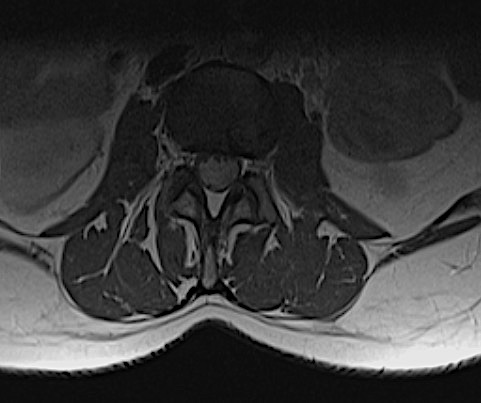

En los cortes axiales se aprecia la lesión ocupando casi todo el volumen tecal, con desplazamiento de raíces a anterior y lateral. Obsérvese el aspecto festoneado de la masa, poco habitual en tumores capsulados